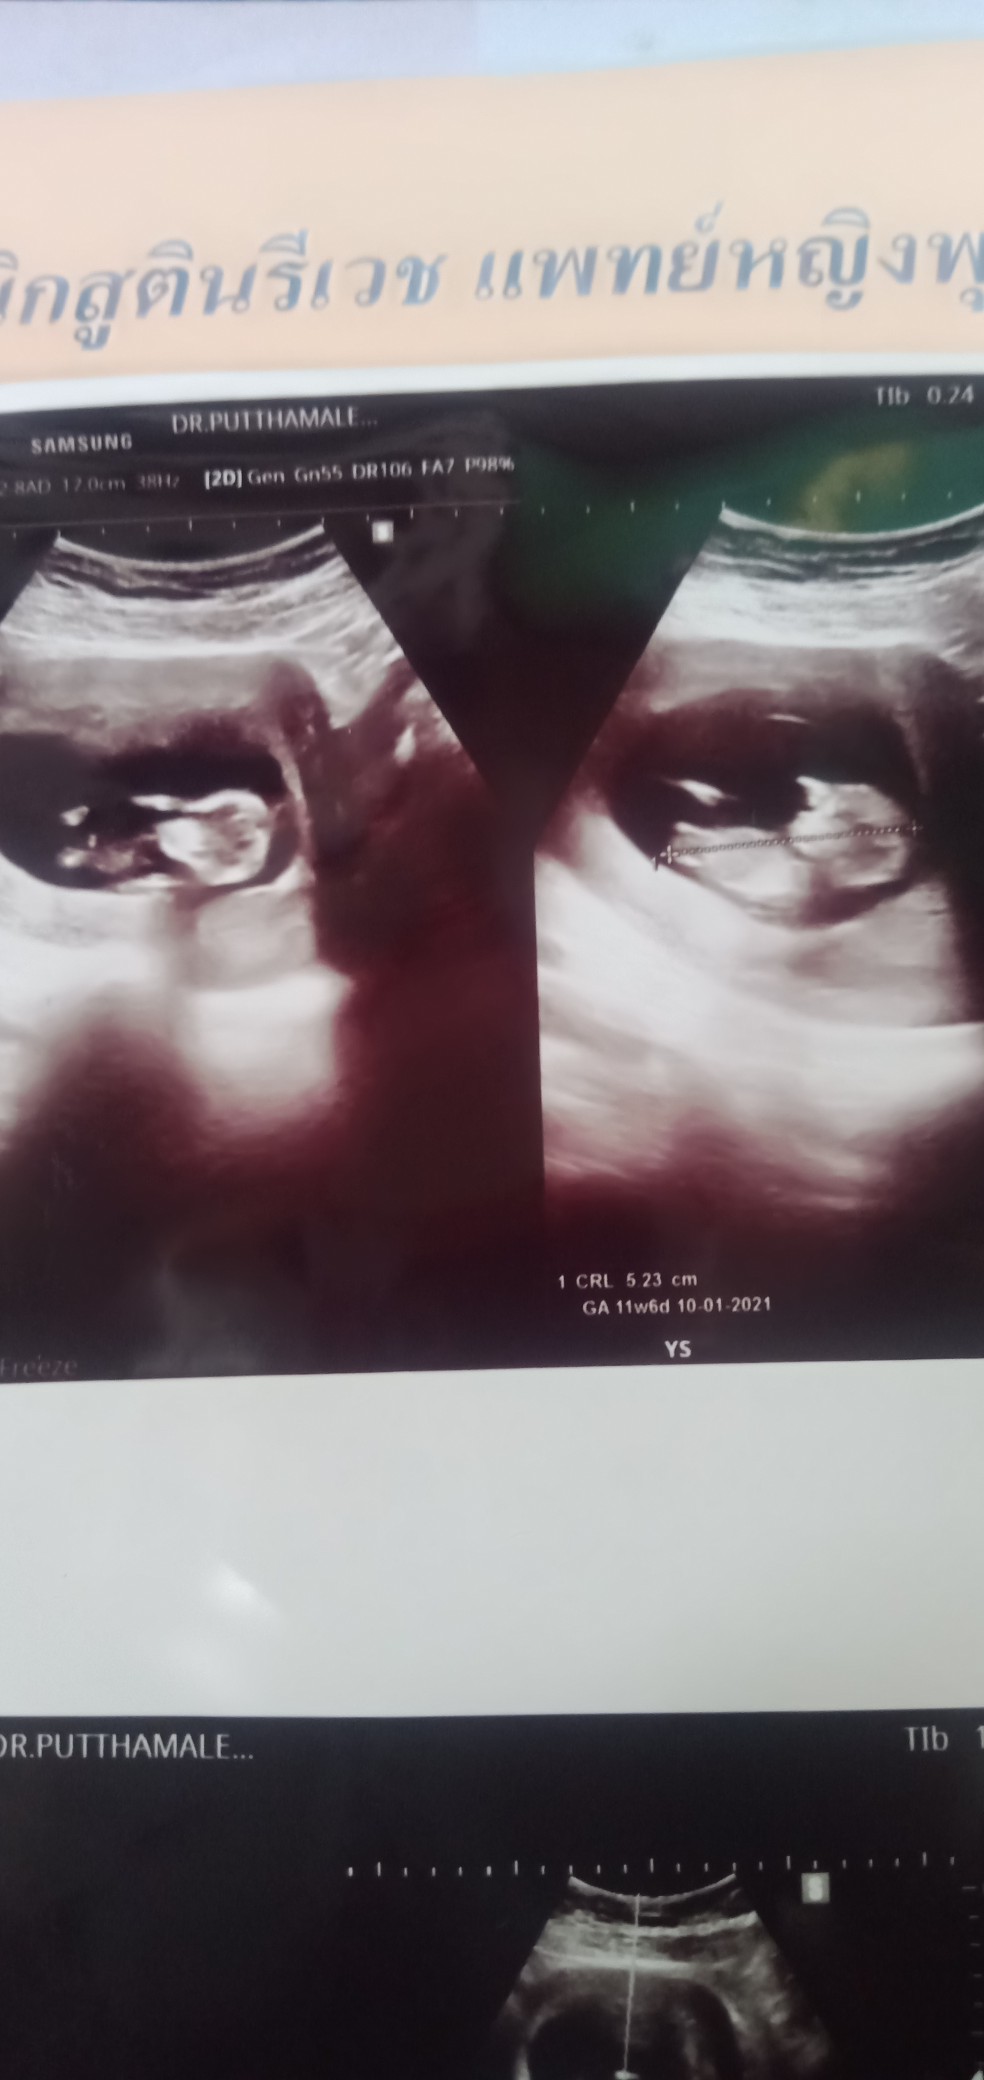

เรา10มกราคมยังไม่สาบเพศ

บ้านนี้ 27 ม.ค ค่าา 11week แล้ว